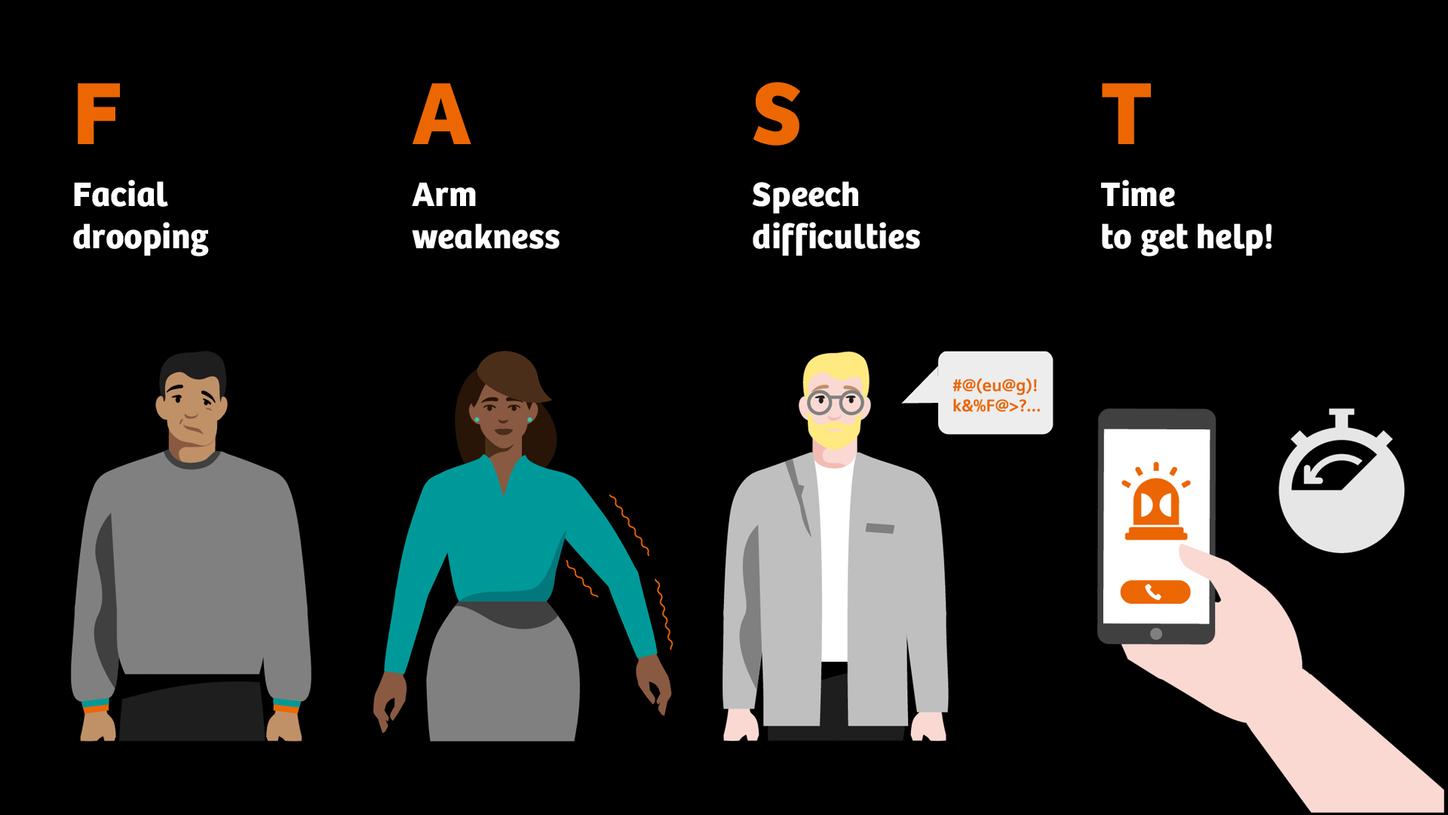

Recognizing early warning signs – FAST

The sooner treatment begins after the onset of stroke symptoms, the better the chance of preventing permanent damage. Recognizing early warning signs – like sudden weakness or numbness on one side, slurred speech, or vision disturbances – can be life-saving. The easy to remember FAST test (Face, Arms, Speech, Time) provides a quick and effective way to identify a potential stroke and act immediately.